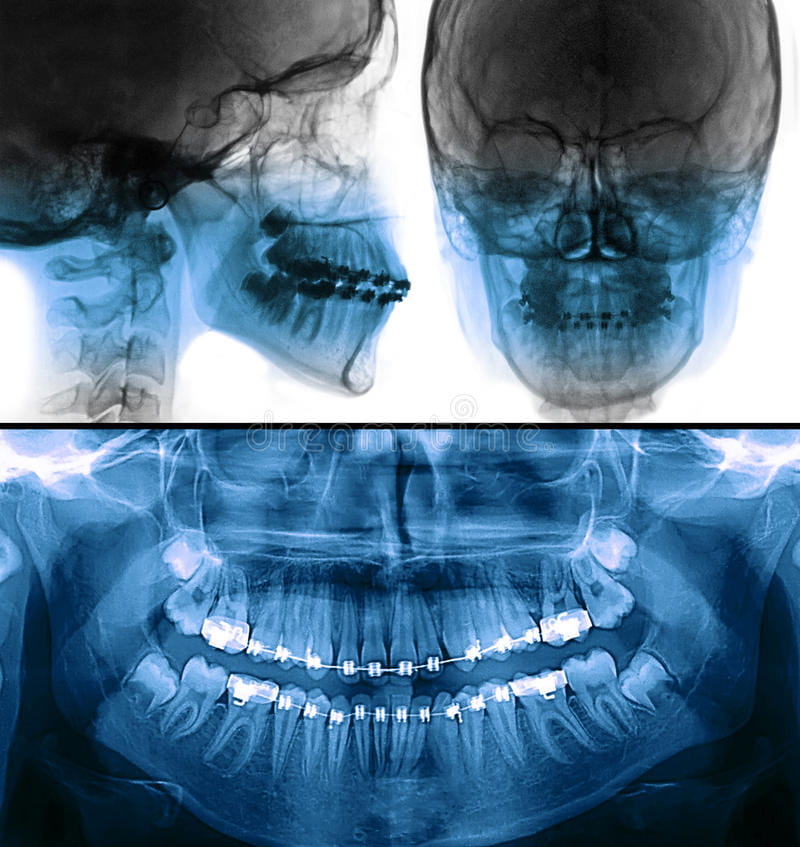

Extra Oral:

- Frente

- Perfil